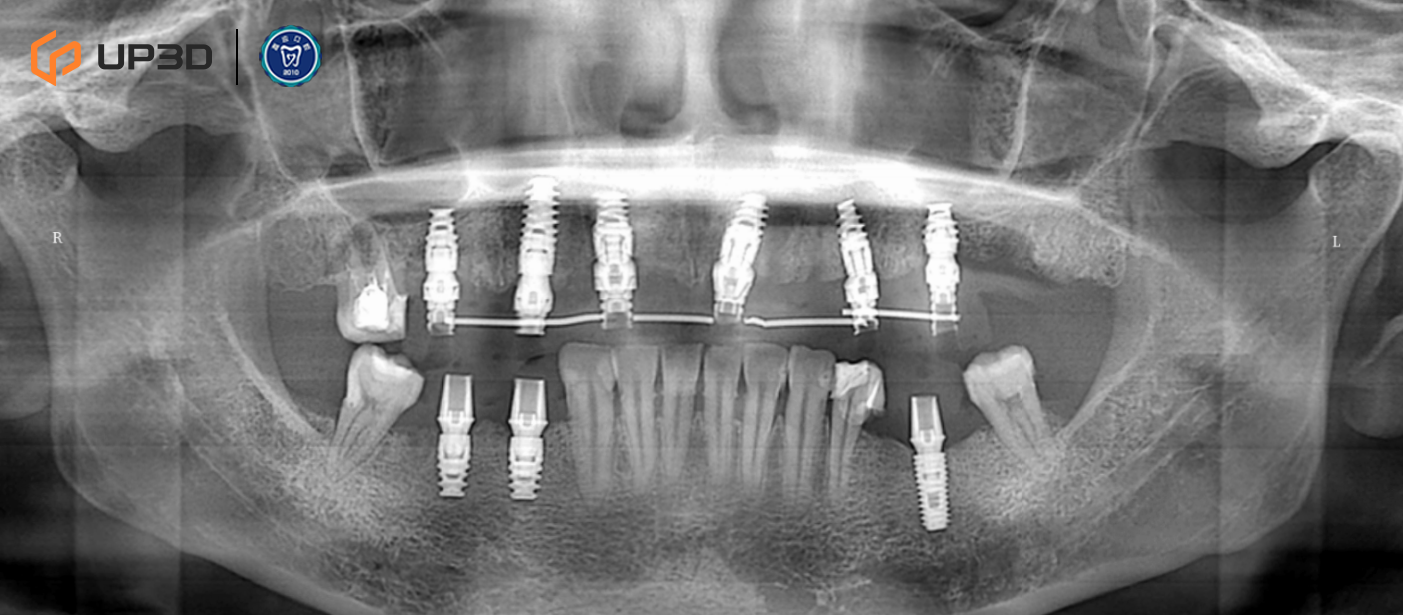

2.3 Radiographic Assessment

A panoramic radiograph and cone-beam computed tomography (CBCT) revealed multiple missing teeth and uneven alveolar ridge resorption, with moderate-to-limited bone volume in selected areas. Based on measurement and analysis, implant placement was planned at sites including 16, 14, 12, 21, 24, 26, 36, 45, and 46 (FDI tooth numbering).

8.2 Three-Month Follow-Up

-

Panoramic imaging showed stable implant and prosthesis positioning

Occlusion remained stable, with no evident peri-implant bone changes on follow-up imaging